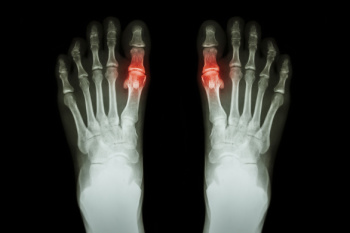

Gout is a form of arthritis that is characterized by sudden, severe attacks of pain, redness, and tenderness in the joints. The condition usually affects the joint at the base of the big toe. A gout attack can occur at any random time, such as the middle of the night while you are asleep.

- Inflammation and Redness -Affected joints may become swollen, tender, warm and red